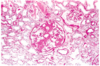

What is the most common and also the most severe pattern of glomerular disease seen in SLE?

Characteristics/morphology?

- Diffuse lupus nephritis (Class IV)

- >50% involvement of Glomeruli

- Proliferation of epithelial cells —> cellular crescents that fill Bowmans space

- Circumferential thickening of capillary wall, forming “wire loop” strucutres on light mircoscopy (see attached photo)